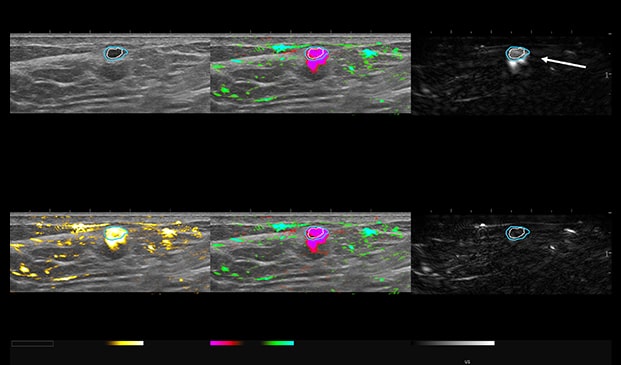

Case Example 4:

53-year-old female, called back for diagnostic imaging. A 5 mm mass seen on ultrasound with complex, negative doppler signal.

Case Example 4: Observations

OA imaging demonstrates an increase in an intense pink colorization with an “eggshell sign” seen on the short wavelength. The raw short wavelength image represents deoxygenated hemoglobin and the long wavelength map in the lower right represents the raw oxygenated Hgb from the two lasers.

The eggshell pattern on the short wavelength is a benign feature, in addition to the intense pink colorization appearing as a uniform bloom versus a polymorphic (disorganized) pattern often seen with malignant masses.

Angiogenesis can be malignant or benign. Here we see physiologic angiogenesis associated with acute inflammation.

- Fibrocystic, Proliferative

- Inflamed Cyst

This patient was biopsied, and results were fibrocystic inflamed cyst. Mass down-classified from BI-RADS 4A to BI-RADS 2.